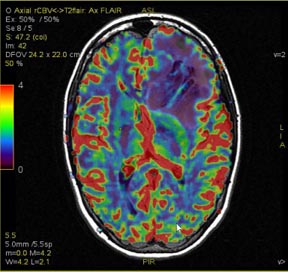

Figure 1. Example of source and map images fused